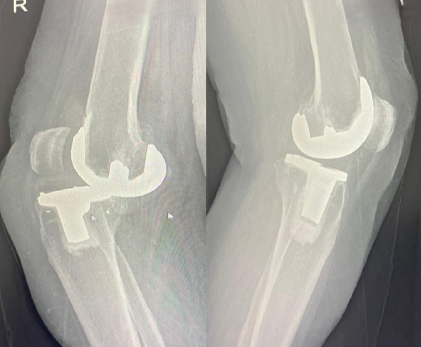

A 63-year-old female presented with pain, swelling, and reduced flexion in the right knee following a fall 2 months earlier. She also reported a 3-year history of recurrent instability, sudden locking, and restricted motion, which she occasionally relieved by self-manipulation. She had undergone bilateral TKR (left knee 15 years ago and right knee 12 years ago) using the Stryker Duracon system. At a local hospital, X-ray imaging, as shown in Figs. 1 and 2, revealed tibial component loosening, polyethylene liner dissociation, and marked osteolysis. Laboratory parameters (complete blood count, erythrocyte sedimentation rate, and C-reactive protein) were normal, excluding infection.

Figure 2: Dislocation is well noted in the lateral right knee X-ray, whereas the left knee appears normal.